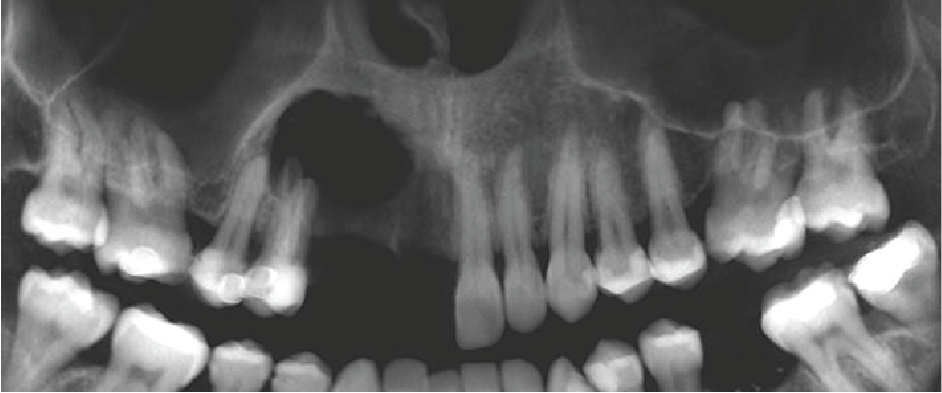

There is a large unilocular moderately well-defined radiolucency, 23 x 15 x 14 mm extending from the UR5 apex to the midline but not invading the nasopalatine canal. There is a “through and through” destruction of the buccal and palatal cortical bony plates, as well as destruction of the alveolar bone ridge. The right maxillary sinus and floor of the nose are not involved. There is external root resorption of the UR4.

The lack of bone expansion, resorption of UR4 roots plus the “floating tooth” appearance of UR4 all suggest the possibility of malignancy. In a case such as this an urgent referral to an oral surgeon is recommended for biopsy to determine the diagnosis and rule out a malignancy.